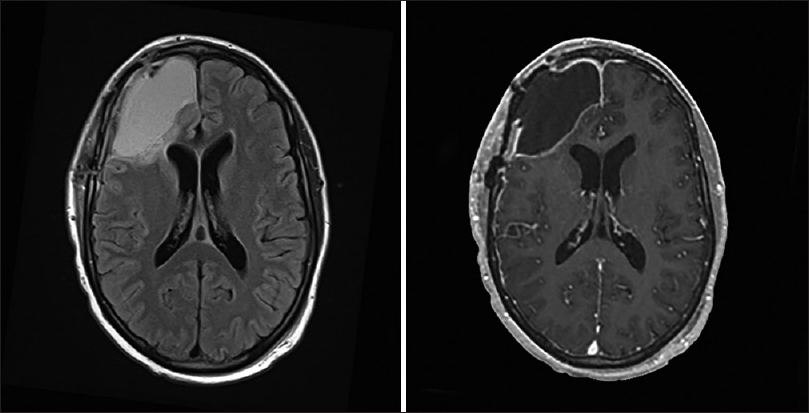

一般来说,除非有明确的指征,否则孕妇应避免进行超声以外的影像学检查。然而,母亲的健康和顺利不应该因为对辐射的担忧而受到危害。孕妇头部的计算机断层扫描(CT)是相对良性的,因为对胎儿的辐射暴露小于0.005 mGy。据估计,对距离扫描仪30厘米或以上的胎儿进行CT扫描所产生的辐射,其剂量比较大允许剂量0.5毫希沃特低2个数量级。因此,母亲头部CT所产生的辐射对胎儿的危害很小。磁共振成像(MRI)不使用电离辐射,被认为对胎儿相对无害。然而,建议仅在妊娠4个月后进行MRI检查。18从实用的角度来看,我们因此倾向于避免在妊娠的前三个月进行MRI随访,而较初的MRI诊断研究,当以提示颅内肿瘤的新发病症状为标志时,则定期进行。获得及时的诊断,可以适当地指导剩余妊娠期的医疗管理,这显然超过了与手术相关的小风险。

不幸的是,MRI和CT的准确性依赖于静脉注射造影剂,这对胎儿的发育至今仍有未知的影响。以碘或钆为基础的静脉造影剂在怀孕期间都没有被证明是完全顺利的。虽然具体的致畸效应尚未在人体中发现或报道,但作为一般规则,这些制剂应仅在必要时使用,且仅在仔细评估风险收益比之后使用。